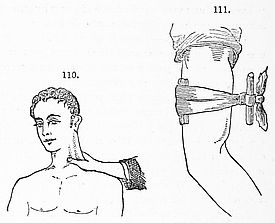

The Sickroom.—The Room; the Nurse; the Bed; Sickroom Accessories; Feeding Patients; Invalid Dishes and Drinks; Administering Physic; Domestic Remedies; Accidents and Emergencies; Bandaging; Burns; Carrying Injured Persons; Wounds; Drowning; Fits; Frostbites; Poisons and Antidotes; Sunstroke; Common Complaints; Disinfection, &c.